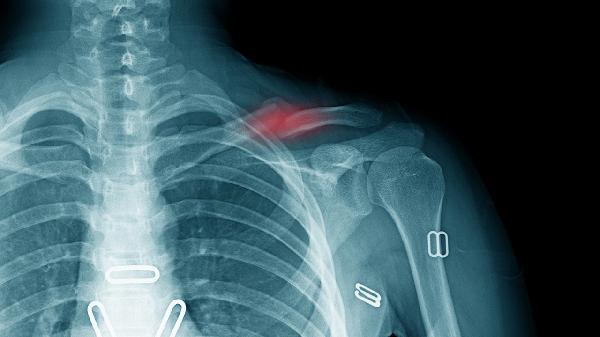

3、并发症预防

重点防范坠积性肺炎,每日进行深呼吸训练和叩背排痰。使用气垫床预防压疮,骨突处贴减压敷料。多饮水并按摩下肢预防深静脉血栓,必要时穿弹力袜。记录排尿排便情况预防泌尿感染和便秘。